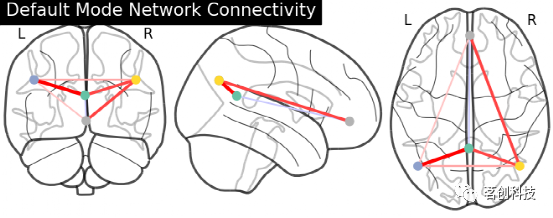

plot_connectome:绘制连接体图像。使用函数nilearn.plot .plot_connectome来显示连接图。

from nilearn import plotting

plotting.plot_connectome(partial_correlation_matrix, dmn_coords,

title="Default Mode Network Connectivity")